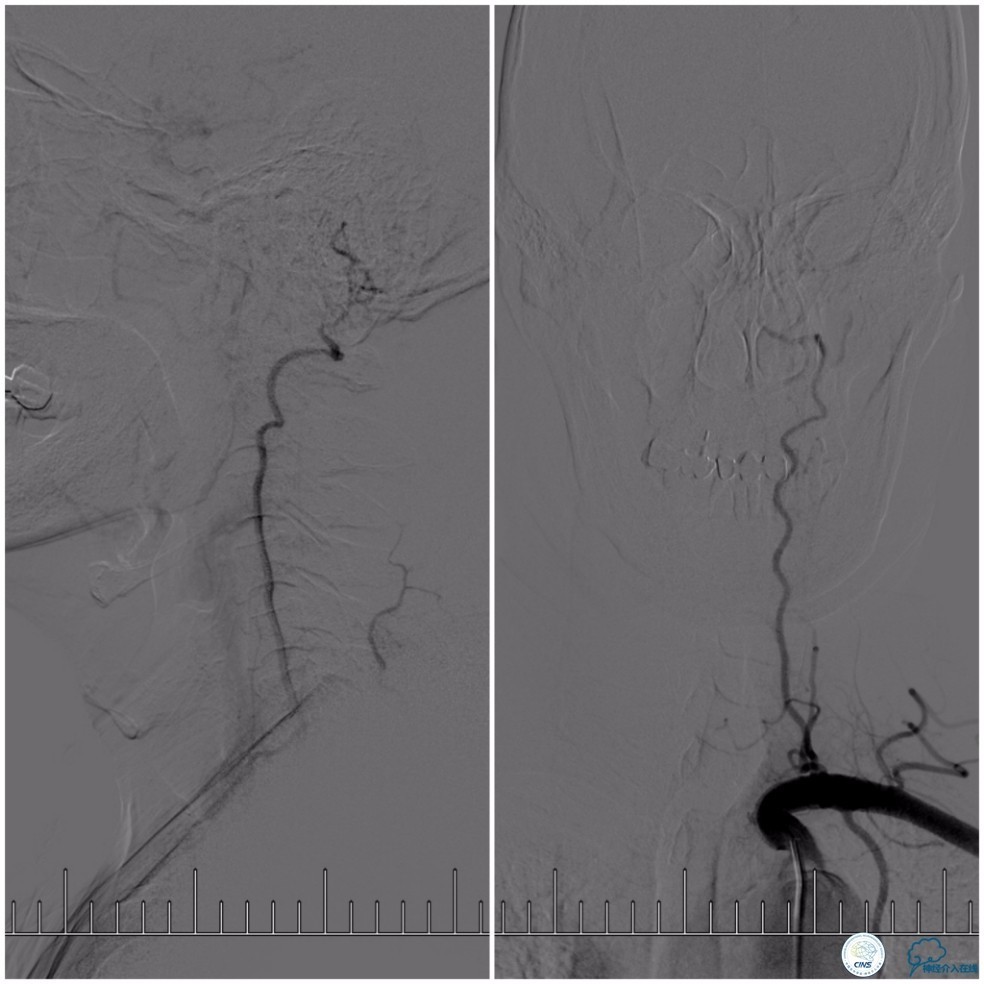

全麻下,右股动脉穿刺,因8F导引导管不能通过右椎动脉V1段,改用6F导引导管置于右椎动脉V2段,穿刺左股动脉放置5F导引导管用于栓塞动脉瘤入路。Transend微导丝(0.014″,300cm)通过基底动脉狭窄段,放置在右大脑后动脉P2段后选择Gateway球囊(2.0mm×15mm)先预扩狭窄(图10)。

图10

Wingspan支架(3.0mm× 20mm)系统到位后,经5F导引导管放置Echelon-10微导管至动脉瘤腔内,释放Wingspan支架,进行动脉瘤栓塞(图11)。

图11